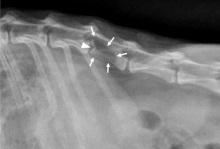

- Mediastinal. A doença afeta os gânglios linfáticos no esterno e no timo do furão, o que pode causar um nó na garganta;

- a formação de crostas escuras no conduto auditivo do animal, conforme foto acima;